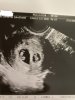

Jestem mega szczęśliwa bo nadal biją dwa serduszka 🥰 jeden pęcherzyk i zarodek jest trochę mniejszy ale gin mówiła że często bliźniaki nie są symetryczne.

Załączniki

• 8D495CF0-420A-4EDC-8D56-F0DDEA7B62A8.jpeg

8D495CF0-420A-4EDC-8D56-F0DDEA7B62A8.jpeg

422,8 KB · Wyświetleń: 139